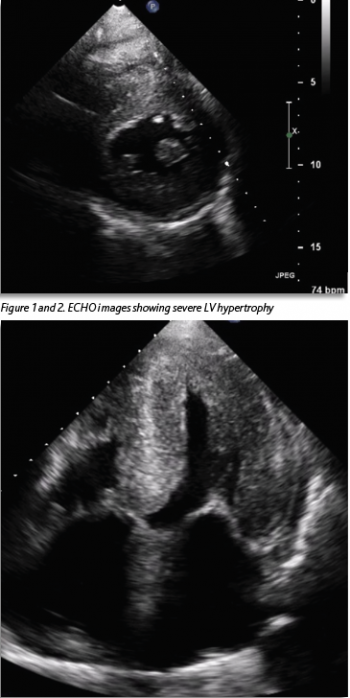

She was known to have severe left ventricular hypertrophy (LVH) with preserved LV function, which had been seen on echocardiogram (ECHO) two years previously (Figures 1 and 2). A coronary angiogram two years previously showed no evidence of coronary artery disease. Her ECG showed a new bifascicular and first-degree heart block compared to one from two years prior (see Figure 3). Troponin level was elevated at 30ng/L, which was stable from the previous admission (32ng/L). Otherwise, laboratory investigations were unremarkable. She had a significant postural drop in systolic blood pressure of 21mmHg on standing. Her medication regimen included aspirin 75mg, lansoprazole 30mg and hydroxycarbamide 500mg. There was no notable family history. She described a similar presentation to another hospital three months previously. Her vital signs were within normal limits. Cardiovascular examination was unremarkable and the patient was euvolaemic.

This case illustrates very well the typical presentation of a patient with ATTR-CM and highlights both the prevailing lack of awareness regarding this condition and the difficulty faced by clinicians in diagnosing it. The patient initially exhibited a range of features commonly associated with ATTR-CM such as left ventricular hypertrophy and preserved ejection fraction on ECHO, conduction abnormalities on ECG, a mild, chronic troponin elevation and discordance between the degree of LV thickness on ECHO and QRS voltage on ECG.5